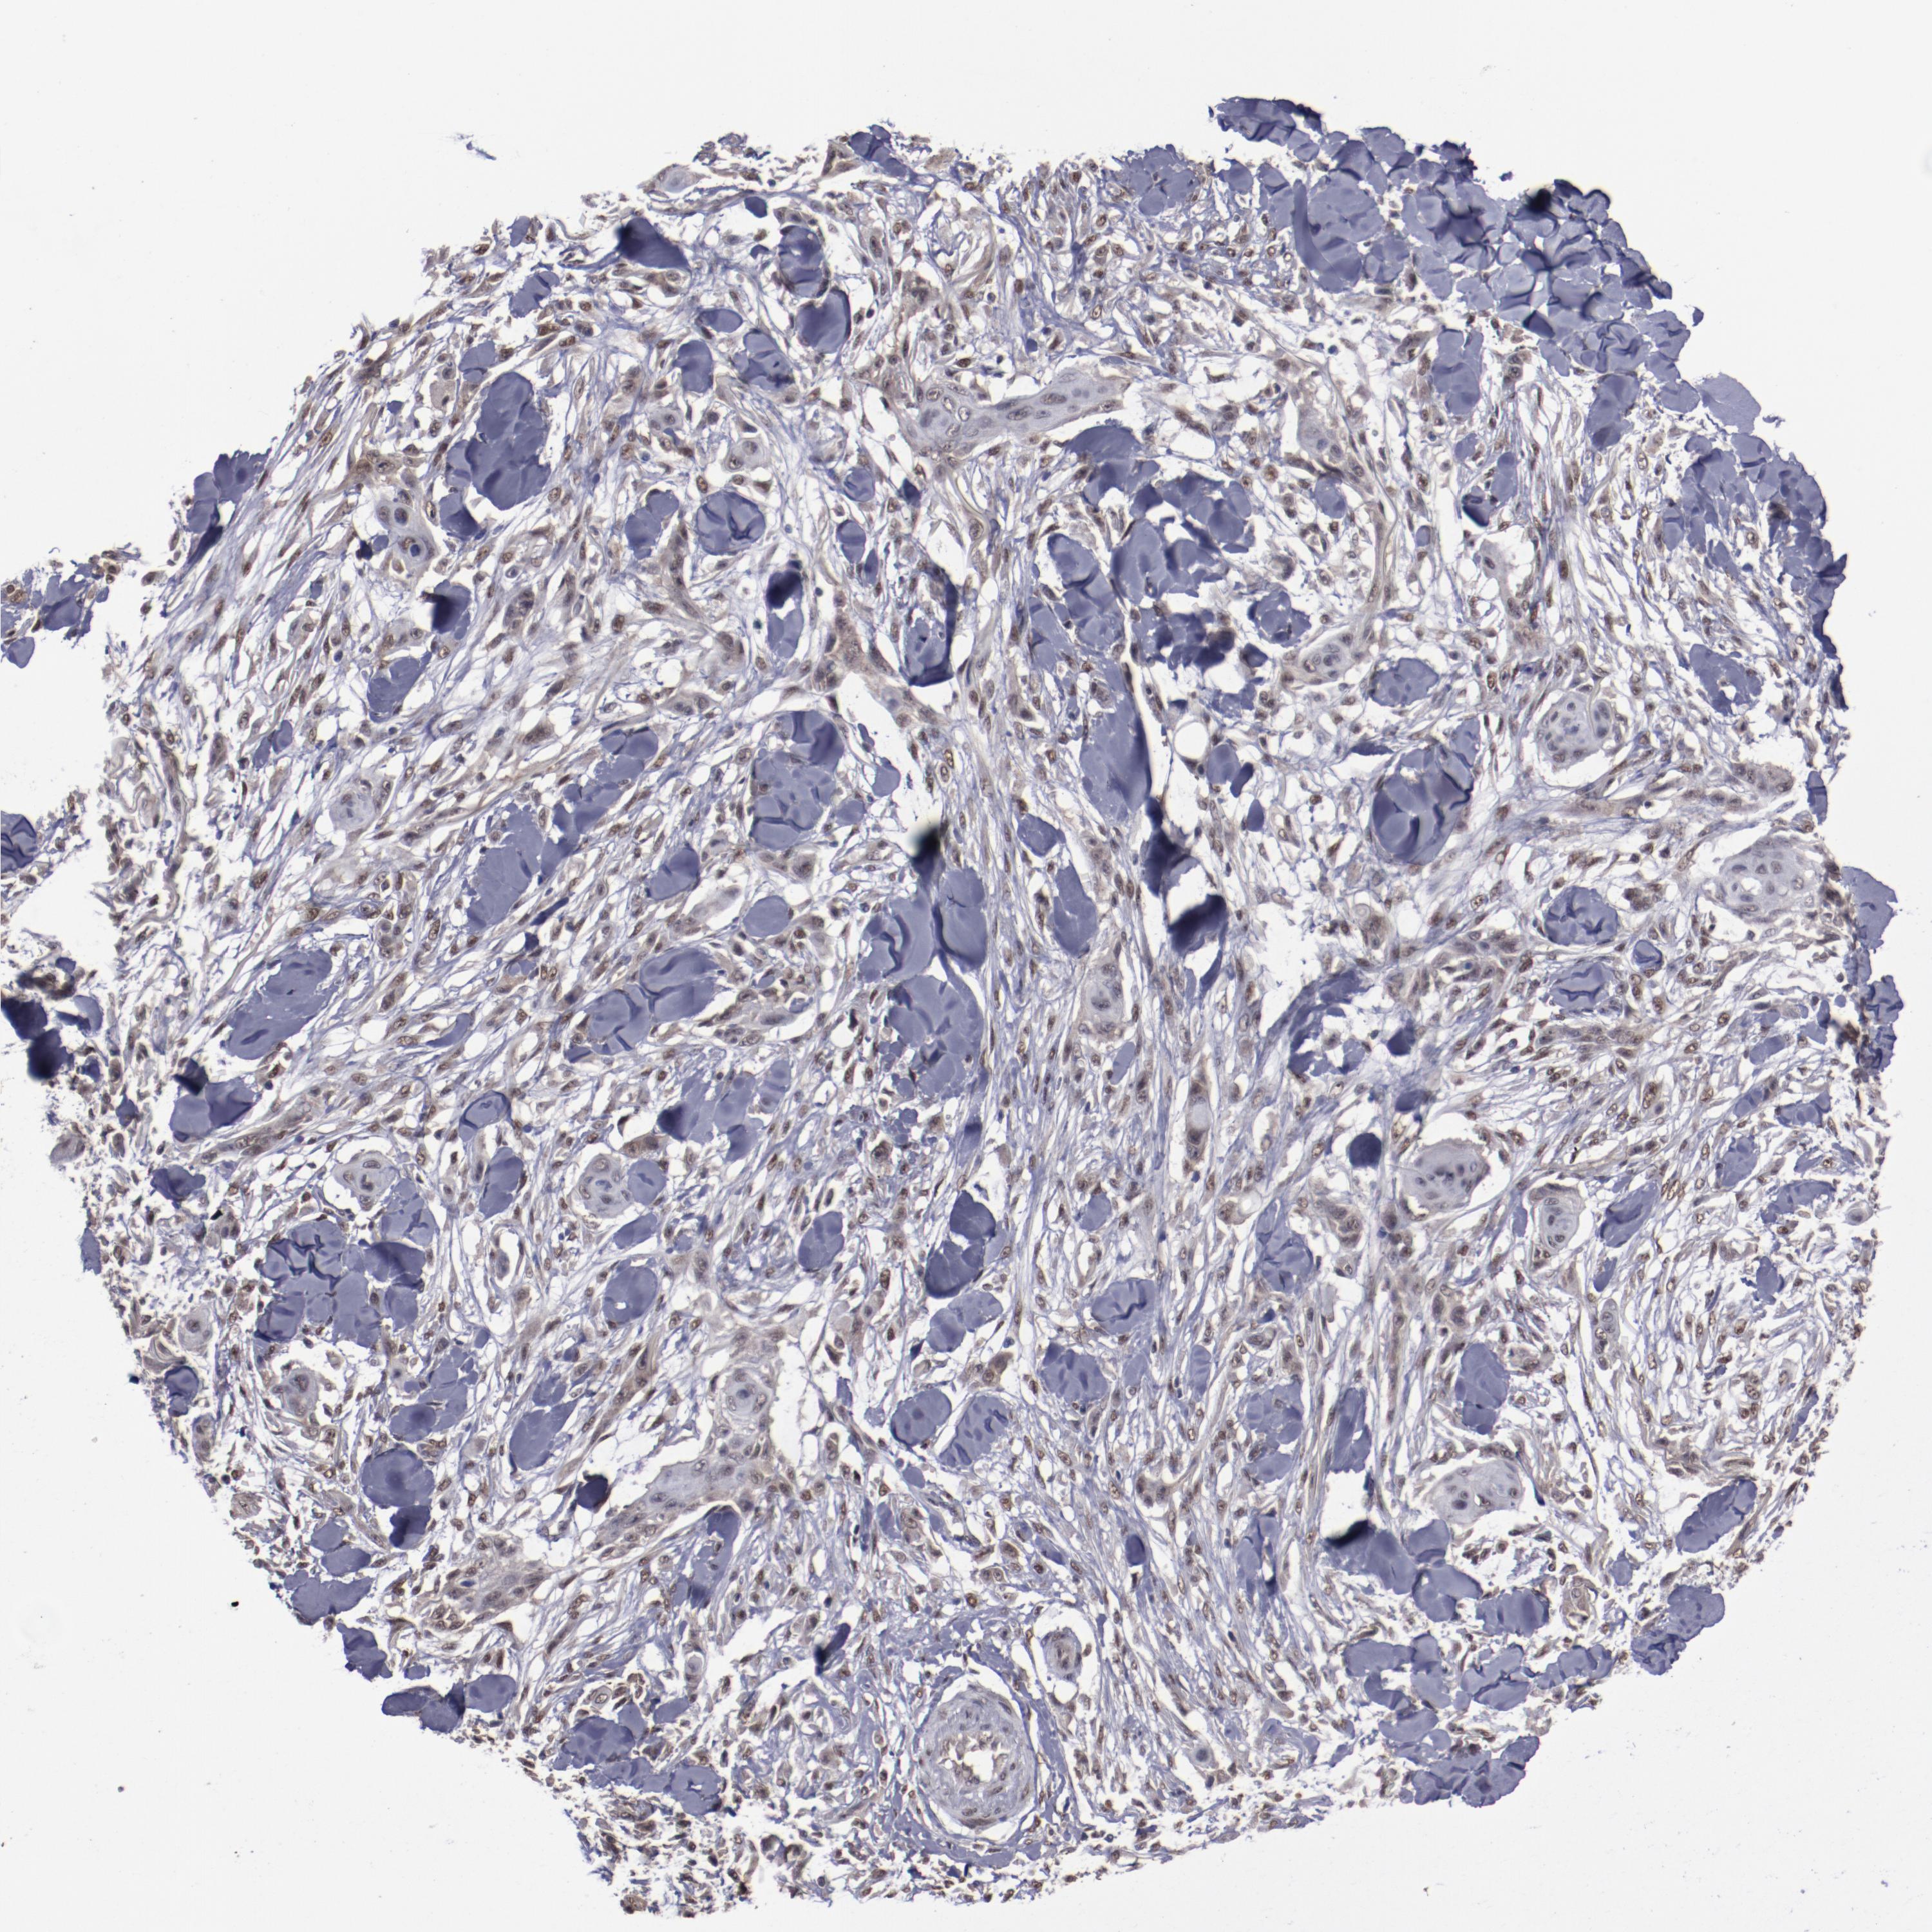

SKIN CANCER - Protein expressioni

A mouse-over function shows sample information and annotation data. Click on an image to view it in a full screen mode. Samples can be filtered based on level of antibody staining by selecting one or several of the following categories: high, medium, low and not detected. The assay and annotation is described here.

Antibody stainingi

Antibody staining in the annotated cell types in the current human tissue is reported as not detected, low, medium, or high, based on conventional immunohistochemistry profiling in selected tissues. This score is based on the combination of the staining intensity and fraction of stained cells.

Each image is clickable and will lead to virtual microscopy that enables deeper exploration of all samples and also displays staining intensity scores, fraction scores and subcellular localization as well as patient and tissue information for each sample.

Antibody HPA001759

Squamous cell carcinoma, NOS